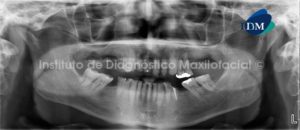

048 – Pansinusitis

Paciente masculino, 56 años de edad acude a Imágenes Digitales (COREF) en Santo Domingo para evaluación tomográfica debido a que presenta supuración a nivel basal